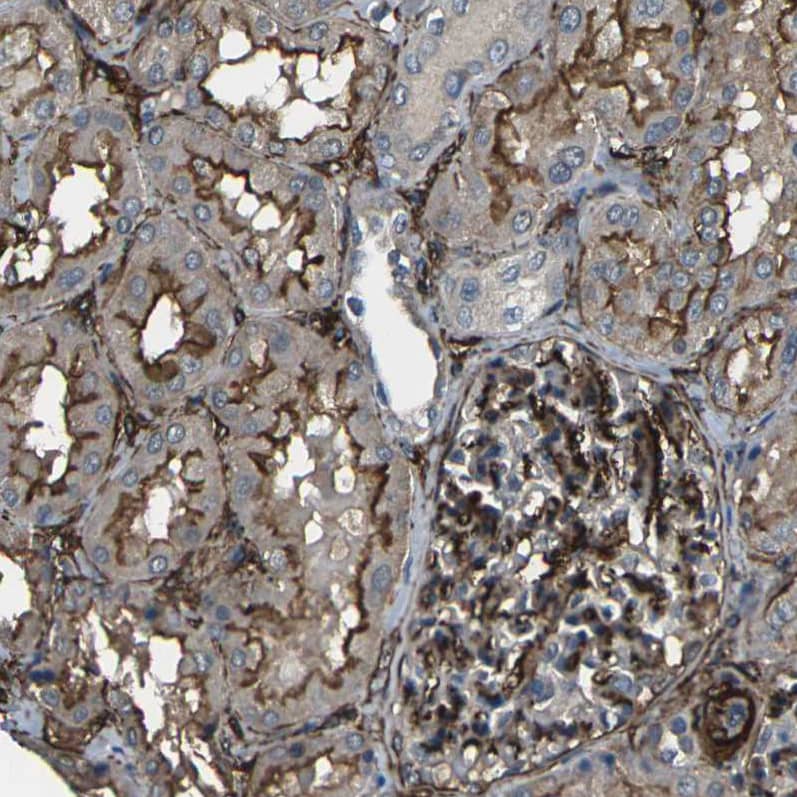

Staining of human kidney shows moderate to strong membranous positivity in cells in tubules and cells in glomeruli.